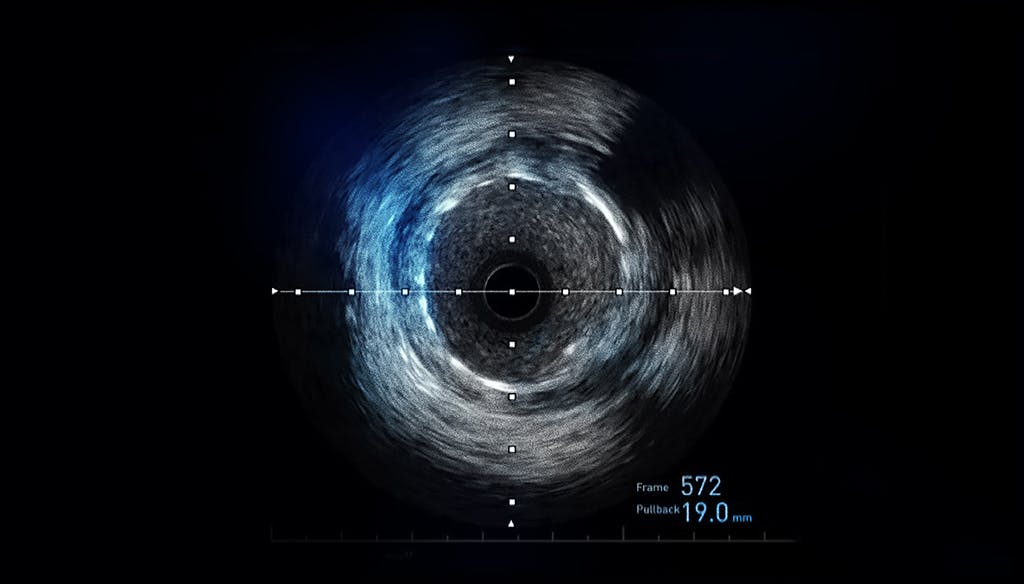

IVUS reprezintă o procedură modernă de vizualizare și evaluare a pereților arterelor coronariene, procedură inovatoare cu rezultate excelente mai ales în cazurile pacienților cu diagnostic de stenoze de trunchi comun.

Cu ajutorul unui un cateter subțire și flexibil dispus cu un transductor care generează ultrasunete și produce imagini, medicul cardiolog intervenționist poate evalua starea leziunilor de pe trunchiul comun sau a stenturilor implantate. Pentru a îmbunătăți rezultatul coronarografiei, ultrasonografia intravasculară vizualizează peretele arterial în întregime. Oferă informații importante despre plăcile de ateromatoză existente la nivelul acestuia. Informațiile și imaginile oferite de sistemul IVUS Eagle Eye îmbunătățesc decizia de tratament. Mai ales, în ceea ce privește dimensiunea stenturilor necesare sau poziționarea exactă a acestora. Sistemul IVUS poate aprecia markerii afecțiunii, inclusiv procentul exact al adâncimii plăcii de aterom. Poate aprecia, de asemenea, localizarea exactă a acesteia cât și morfologia sau volumul de calciu. Suplimentar, poate analiza parametrii cruciali cum sunt măsurătorile în secțiunea transversal-luminală. De asemenea, sistemul ChromaFlo permite o evaluare a dimensiunii lumenului și este adecvat atât pentru vasele periferice cât și pentru cele coronare.

Tehnica IVUS se efectuează în sala de angiografie, fără a folosi însă radiația ionizată, ca în cazul coronarografiei. Acest sistem nu are efecte secundare și generează imagini clare. Chiar și în cazul țesuturilor moi care nu sunt vizibile de obicei la radiografie.